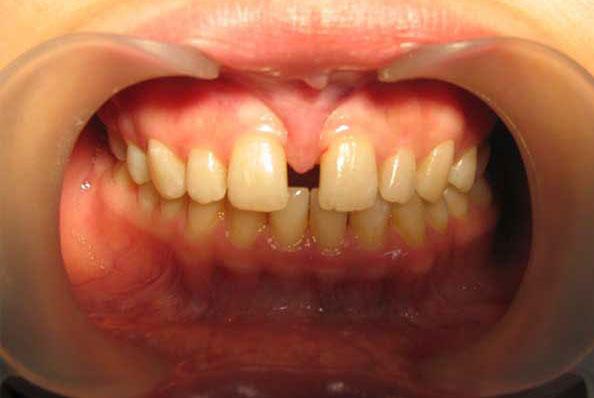

- Укороченная уздечка губы, а также ее близкое крепление к краю альвеолярного отростка становятся причиной оттягивания межзубных сосочков десны в пространстве между резцами. В результате в костной ткани между лунками зубов формируется щель – диастема. Кроме того, увеличивается расстояние между коронками.

- При наличии диастемы (щели) между центральными резцами. Вплетенная в межзубный сосочек и формирующая толстый тяж уздечка верхней губы не дает резцам сходиться к центру. К тому же воздействие небольшой постоянной нагрузки приводит к постепенному увеличению диастемы и смещению зубов вперед и в стороны от центра, а также развитию пародонтита вследствие постоянного травмирования межзубного сосочка.

- Улыбка до и после пластики уздечки